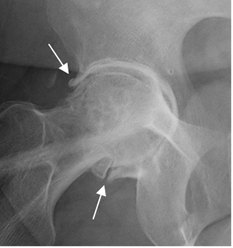

Fig 102. Pinzamiento tipo cam.

Rx AP de pelvis. Prominencia bilateral, en la parte externa de ambas cabezas femorales, que produce pinzamiento tipo cam.